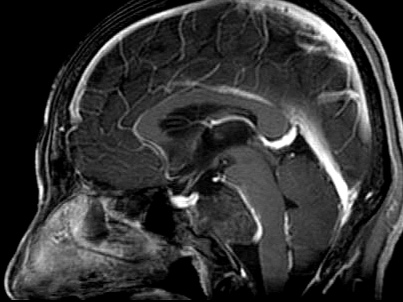

女性患者,56岁,因“视物重影4月”于2023-07-11入院。

入院诊断:斜坡脊索瘤